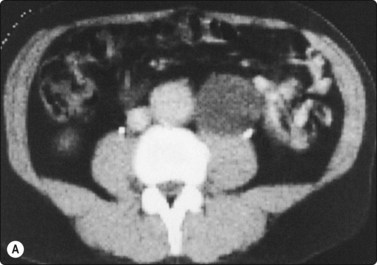

Cystic lymphangioma135

Smears of fluid aspirated from a cystic lymphangioma contain only lymphoid cells, mainly small lymphocytes, in variable numbers. A case from our files is illustrated in Figure 12.41.

image image

Fig. 12.41 Cystic lymphangioma, retroperitoneum

(A) Abdominal CT scan; low-density round lesion left of aorta; (B) Smear of cyst fluid; numerous mainly small lymphocytes (MGG, HP).

A 66-year-old man was investigated for suspected abdominal aortic aneurysm. A CT scan demonstrated a round mass below the left kidney between the aorta and the psoas muscle which was clearly separated from the aorta (Fig. 12.41A). The mass appeared to be cystic on ultrasonography. FNB yielded milky fluid and the mass decreased considerably in size. Smears of the fluid showed numerous normal lymphocytes. A diagnosis of cystic lymphangioma was made, there was no surgical intervention and follow-up was uneventful.